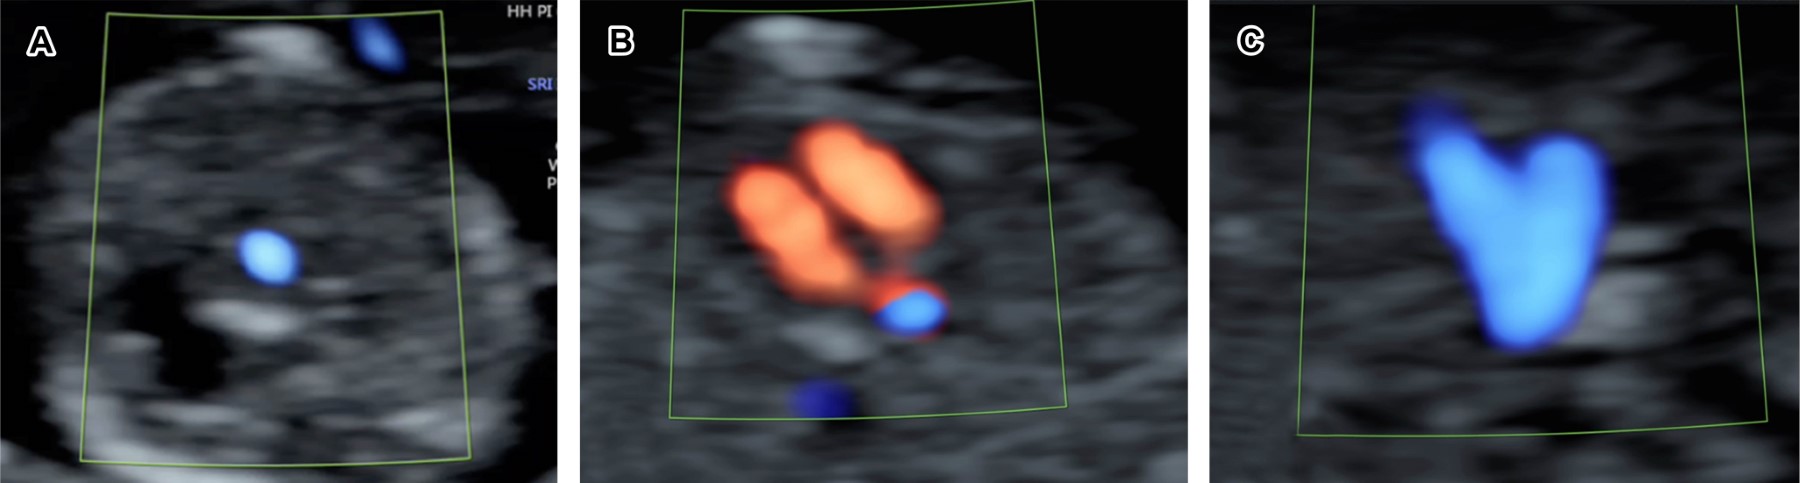

Figure 2